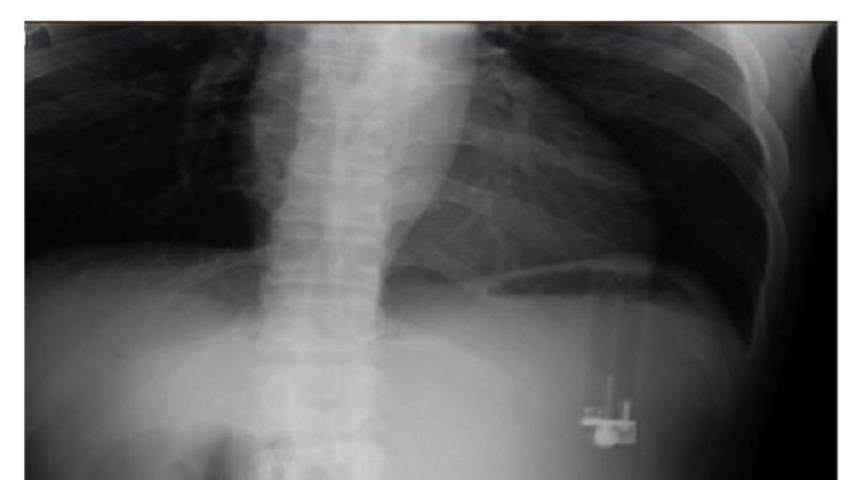

Amerika'da bir adam, karnındaki ağrının sebebinin daha önce yuttuğu bir çakmak olduğunu ve çakmağın midesine zararlı bir sıvı akıttığını öğrendi. Ağustos 2016'da şiddetli karın ağrısı, mide bulantısı ve istifra şikayetleriyle hastaneye giden 49 yaşındaki Amerikalı adama yapılan kan ve idrar testleri temiz çıkarken, röntgen sonuçlarında çakmak benzeri bir madde görüntülendi.

Ağustos 2017'de Case Reports in Emergency Medicine dergisinde yayınlanan makalede, "röntgende görüntülenen çakmağın" adamın midesinde ters bir şekilde durduğu ve mideye zehirli ve kimyasal bir sıvı akıttığı söylendi. Bu sıvı, 49 yaşındaki adamın midesinde en genişi 5 mm olmak üzere, birçok gastrit-ülser yarası oluşmasına sebep oldu.